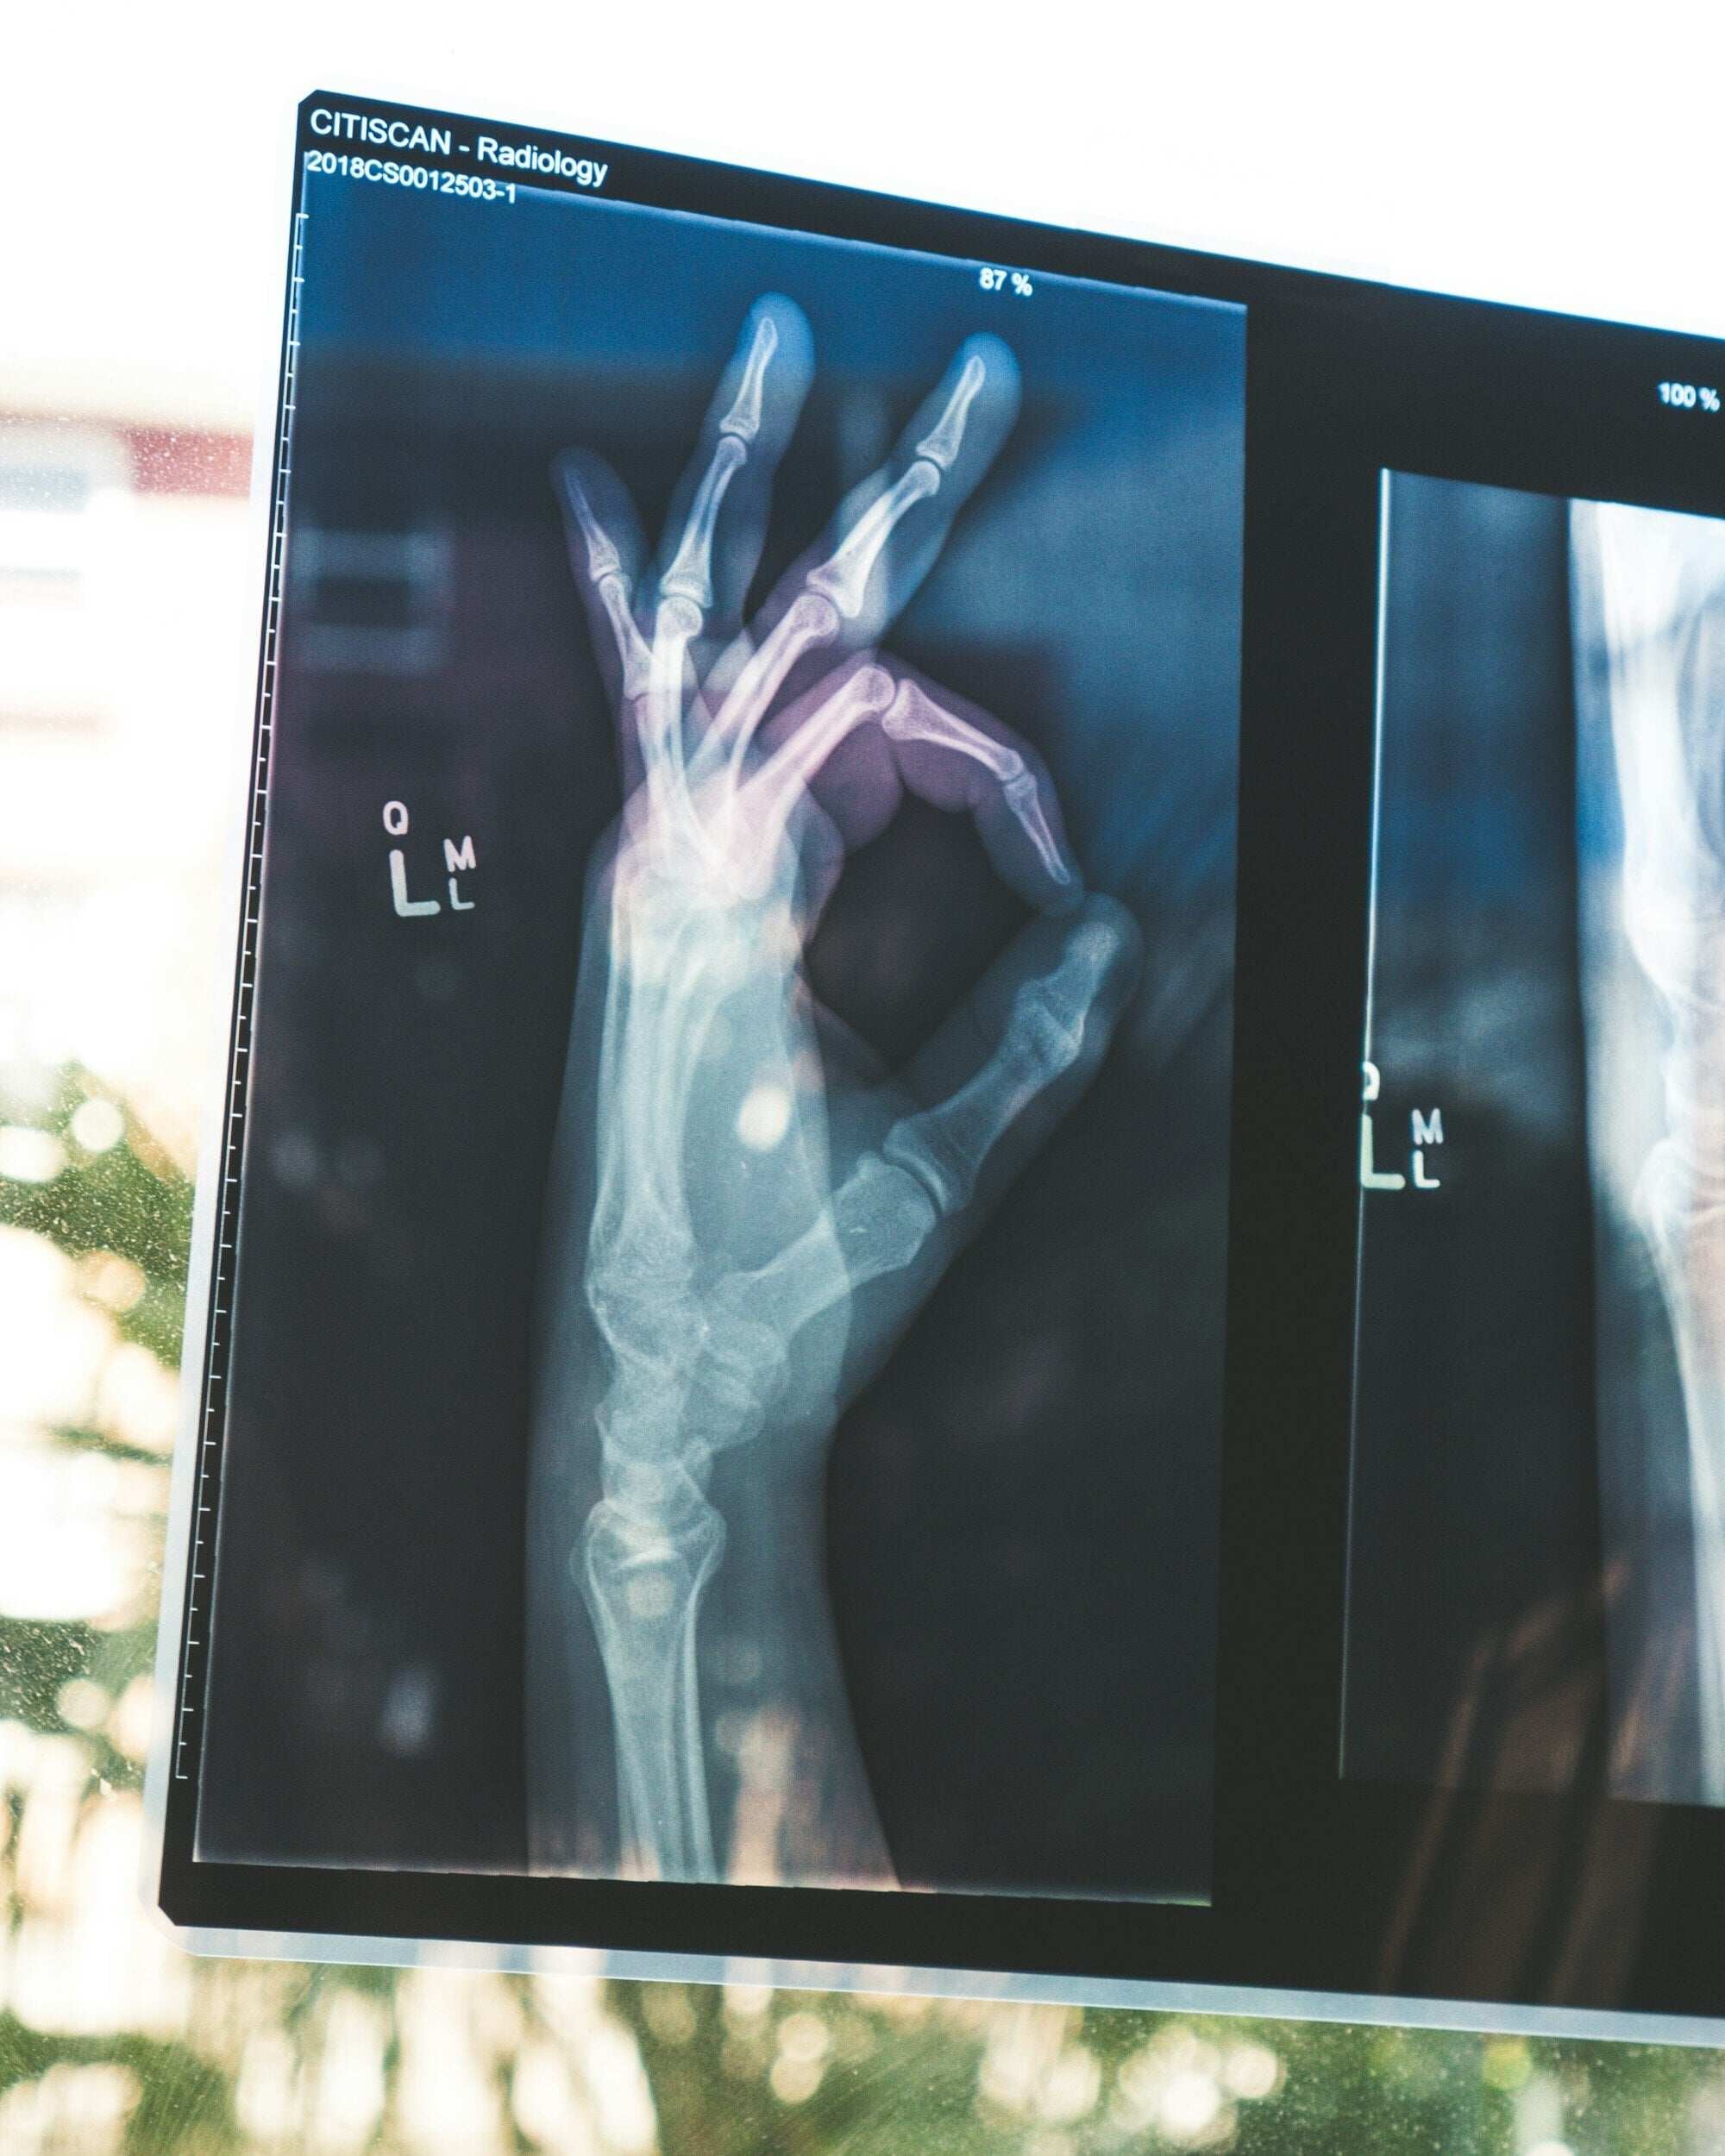

Xray of hand giving OK sign